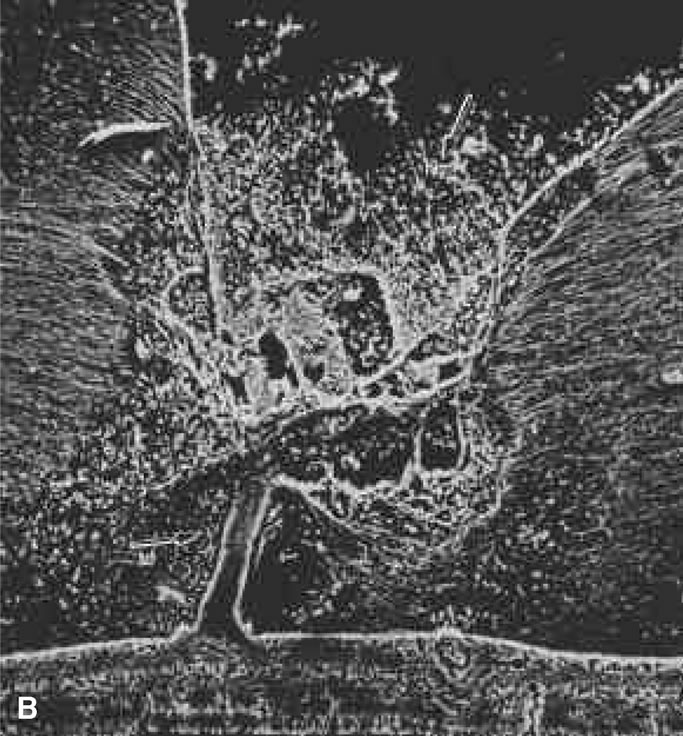

Fig. 10. A. Cystic retinal tuft. The tuft is a cystoid formation of fibers, similar to those of the nerve fiber layer, and cells similar to those found in the inner plexiform layer of the retina. The tuft is connected to the internal limiting lamina of the retina. This scanning electron micrograph shows the insertion of the vitreous collagen fibers on the tuft's apical surface. Their orientation changes toward the tuft's surface. B. Verruca. The verruca has a structure similar to that of a tree. Its “roots” are embedded in the inner layers of the retina. Cellular elements resembling cells of the inner plexiform layer can be seen near the retinal surface. The “trunk” of this structure extends from the retina to the middle parts of the vitreous cortex. The “branches” of the verruca are intertwined with interrupted vitreous collagen fibers. Local condensation of collagen fibers exists as well as local collagen destruction (arrows) and interruption of the internal limiting lamina of the retina. (Photographs courtesy of Dr. Stephan Dunker.153)